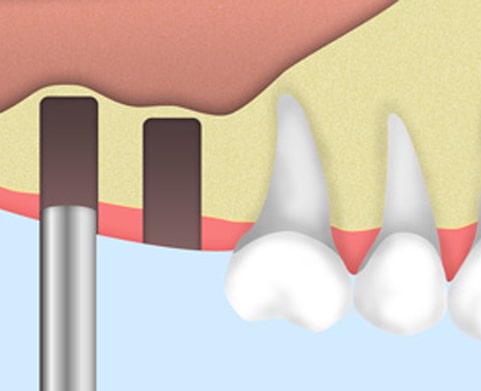

歯槽骨にドリルで穴を開けます。1mmの歯槽骨残した状態で、穴を掘るのを止めます。

あごの骨にフィクスチャー(歯根部)を埋め込みます。

局部麻酔で行うため痛みはほとんどありません。入院の必要もありません。